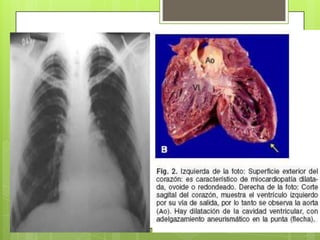

Los trastornos                   Los pacientes con

electrocardiográficos indican             daño severo del

alteraciones en la                     miocardio

Forma crónica

repolarización ventricular y           desarrollan enormes

cardíaca

bloqueo de rama derecha,                   aumentos del

extrasistolia ventricular y            músculo cardíaco

bloqueo auriculoventricular.              (cardiomegalia).